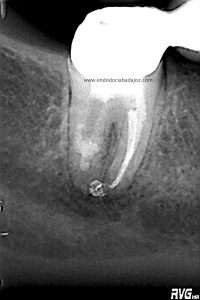

Hemos llamado a revisión a la paciente en varias ocasiones ( 6 meses y 9 meses)

(revision a los 6 meses) (revisión a los 9 meses)

Como podemos observar, la lesión periapical ha regenarado: